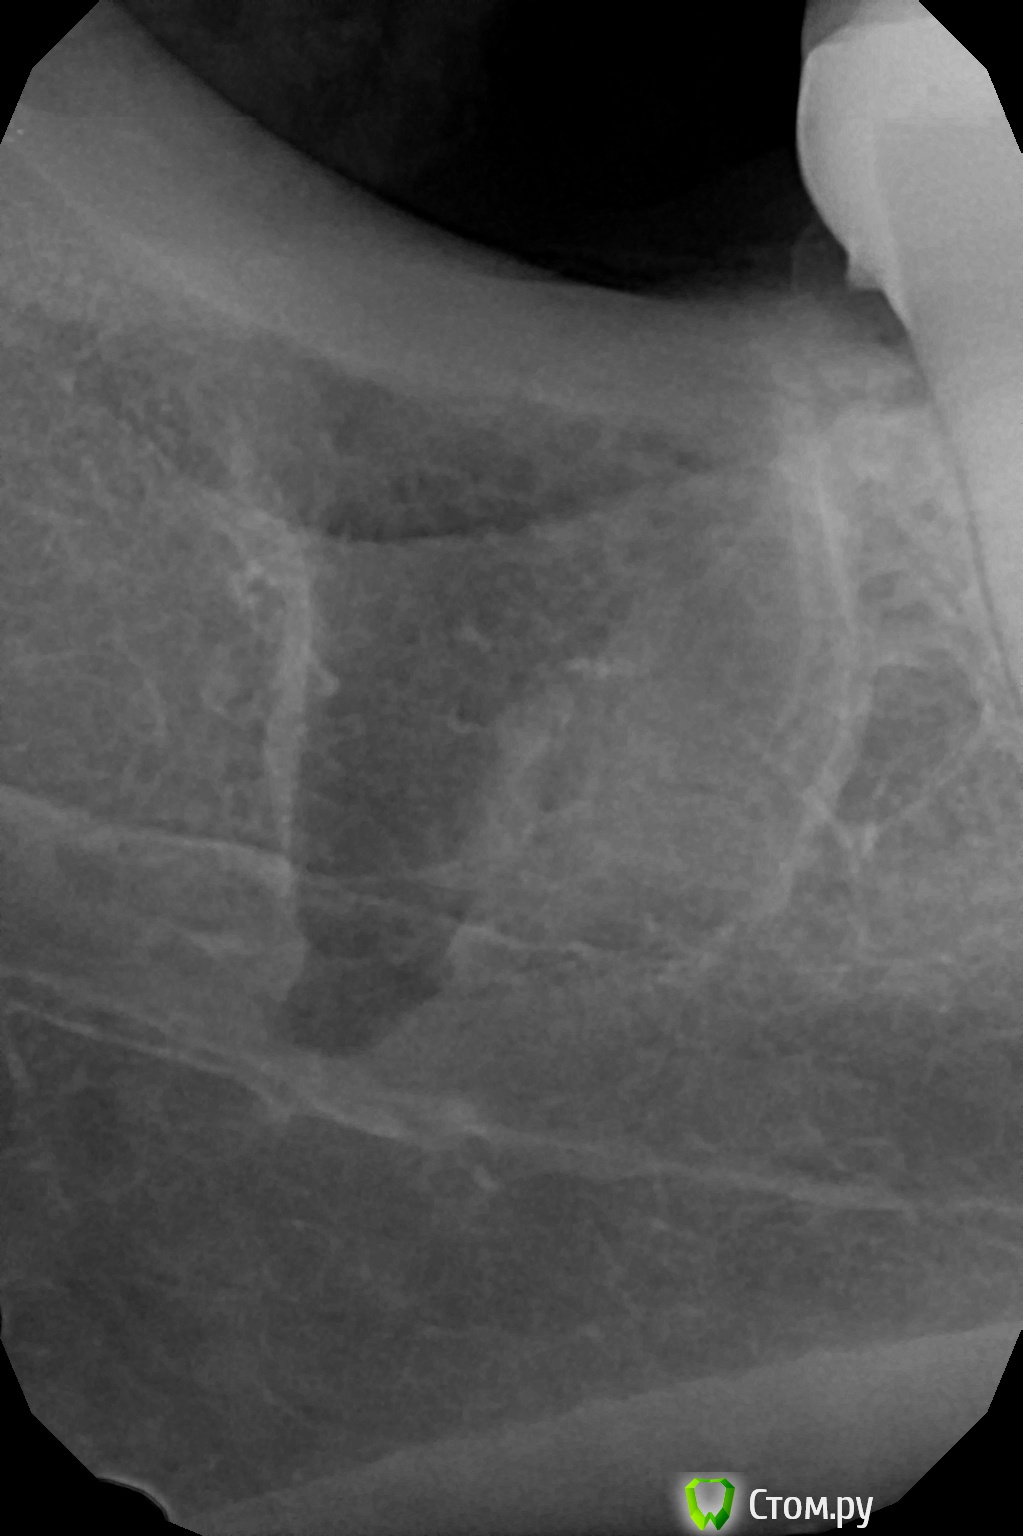

Ayrat_zub Опубликовано 22 сентября, 2014 Поделиться Опубликовано 22 сентября, 2014 Угадайте какой зуб ? два премоляра Ссылка на комментарий

Рубцова Опубликовано 22 сентября, 2014 Поделиться Опубликовано 22 сентября, 2014 верхний 4 или 5 ? Ссылка на комментарий

Большой Зеленый Опубликовано 22 сентября, 2014 Поделиться Опубликовано 22 сентября, 2014 18 19 3 Ссылка на комментарий

faity Опубликовано 24 сентября, 2014 Поделиться Опубликовано 24 сентября, 2014 пам-пам-парарам, привет чужое ЛПУ)))лунка визуально чистая была, АВ лежала строго в щеку, по результату, без бино вообще не видно 7 Ссылка на комментарий

faity Опубликовано 25 сентября, 2014 Поделиться Опубликовано 25 сентября, 2014 лунка визуально чистая была, АВ лежала строго в щеку, по результату, без бино вообще не видно Каким инструментом убрали . СпсАпекальный элеватор и зонд Ссылка на комментарий

Аслан Опубликовано 26 сентября, 2014 Поделиться Опубликовано 26 сентября, 2014 Думате была острая необходимость этот апекс убирать? Считается, что до 2 мм иногда можно забыть. Я оставлял раз 5... не видел и/или оооочень близко канал или пазуха. Ссылка на комментарий

faity Опубликовано 26 сентября, 2014 Поделиться Опубликовано 26 сентября, 2014 Думате была острая необходимость этот апекс убирать? Считается, что до 2 мм иногда можно забыть. Я оставлял раз 5... не видел и/или оооочень близко канал или пазуха.Болел, пух, по показаниям короче 1 Ссылка на комментарий